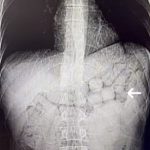

Bahse konu şahısların çekilen tomografi görüntülerinde, mide ve bağırsak bölümlerinde yabancı cisimlere rastlandı.

Yaklaşık 3 gün süren kontroller sonucunda şahıslardan; 91 kapsül halinde 807,15 gram Metamfetamin maddesi ele geçirildi ve şüpheliler gözaltına alındı.